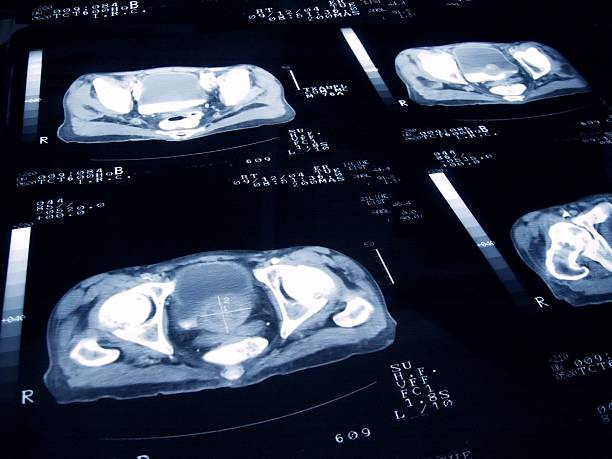

- PSA 검사: 혈액 검사를 통해 전립선 특이 항원(PSA) 수치를 측정하는 검사입니다. PSA 수치가 높으면 전립선암을 의심해볼 수 있어요.

- 직장수지검사: 의사가 손가락을 항문에 넣어 전립선을 직접 만져보는 검사입니다. 전립선의 크기나 모양, 단단한 정도 등을 확인할 수 있습니다.